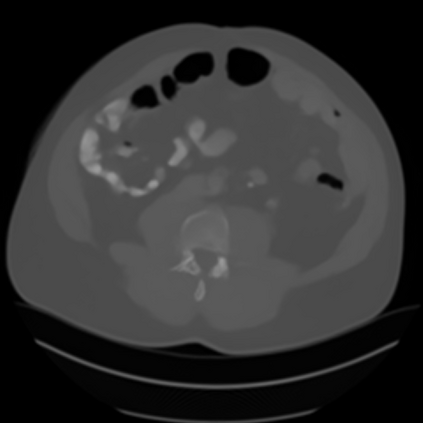

Sparse-view computed tomography (CT) -- using a small number of projections for tomographic reconstruction -- enables much lower radiation dose to patients and accelerated data acquisition. The reconstructed images, however, suffer from strong artifacts, greatly limiting their diagnostic value. Current trends for sparse-view CT turn to the raw data for better information recovery. The resultant dual-domain methods, nonetheless, suffer from secondary artifacts, especially in ultra-sparse view scenarios, and their generalization to other scanners/protocols is greatly limited. A crucial question arises: have the image post-processing methods reached the limit? Our answer is not yet. In this paper, we stick to image post-processing methods due to great flexibility and propose global representation (GloRe) distillation framework for sparse-view CT, termed GloReDi. First, we propose to learn GloRe with Fourier convolution, so each element in GloRe has an image-wide receptive field. Second, unlike methods that only use the full-view images for supervision, we propose to distill GloRe from intermediate-view reconstructed images that are readily available but not explored in previous literature. The success of GloRe distillation is attributed to two key components: representation directional distillation to align the GloRe directions, and band-pass-specific contrastive distillation to gain clinically important details. Extensive experiments demonstrate the superiority of the proposed GloReDi over the state-of-the-art methods, including dual-domain ones. The source code is available at https://github.com/longzilicart/GloReDi.